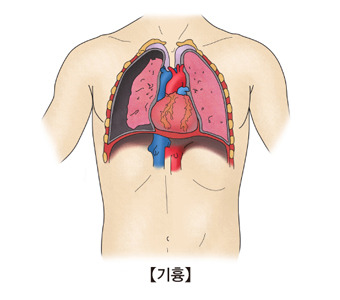

기흉이란 무엇일까?

우리의 폐는 공기로 채워졌다가 비워지는 풍선 같은 기관이에요.

이 폐는 **흉막(pleura)**이라는 얇은 막으로 둘러싸여 있고, 그 사이에는 소량의 윤활액이 있어 폐가 부드럽게 움직일 수 있게 도와줍니다.

그런데 어떤 이유로든 폐에 구멍이 생겨 공기가 흉막 안(흉강)에 새어 나오면, 그 공기가 폐를 압박해 폐가 쪼그라들게 되는 현상이 바로 기흉이에요.

쉽게 말해, **‘폐가 터져서 공기가 새나간 상태’**라고 이해하시면 됩니다.